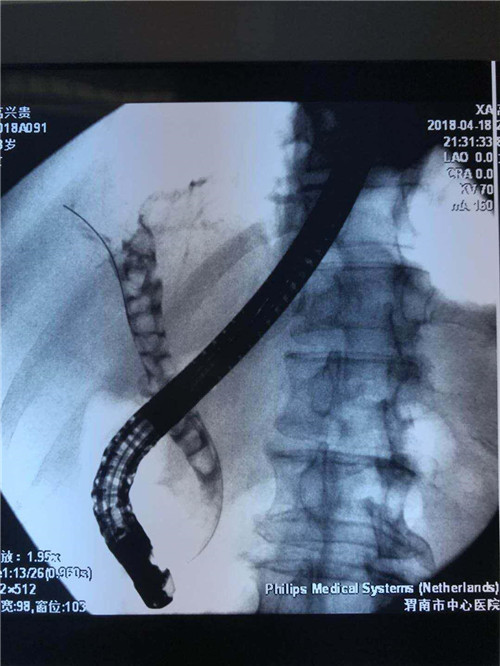

消化内镜中心的曹鹏医生立即向科室王宇晖主任、王莹主任汇报后,并通知李侠护士长做好术前准备工作,为患者开通绿色通道。在介入科的积极配合下,大家迅速到岗。当得知患者75岁高龄,有腹痛、恶心,呕吐伴发热,体温39摄氏度,同时伴有寒颤,手术存在很大风险,曹鹏医生立即制定手术方案,依靠经验和反复不断的内镜下判定,迅速插管成功,置入鼻胆引流管,在引流出大量黄白色脓液的那一刻,患者脸上露出了笑容,成功完成了这台ERCP手术。

曹鹏医生进十二指肠镜后看到肿大的乳头,利用切开刀+导丝超选进入胆管,行十二指肠乳头切开,随即大量脓性胆汁流出,并迅速留置鼻胆管。功夫不负有心人,终于,在主管护师许晓庆、护士王欣的配合下,又成功挽救了一名病患的生命,同时也彰显了市中心医院消化内镜中心医护人员极高的专业素养和娴熟的业务能力。